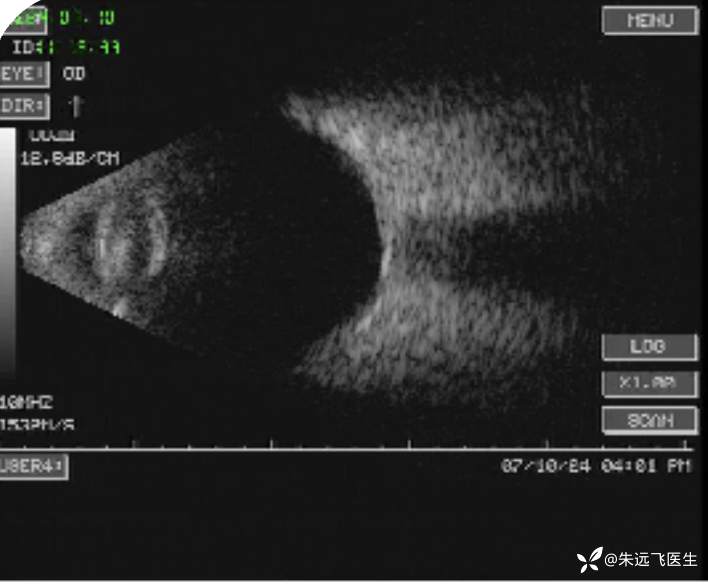

B超未见明显异常。